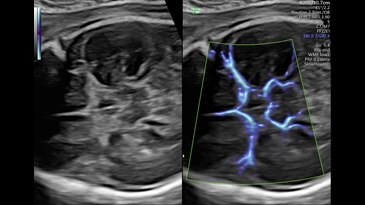

Radiantflow

Новое поколение цветового допплера Radiantflow упрощает и ускоряет исследование, улучшает визуализацию мельчайших сосудов. Алгоритм построения изображения учитывает амплитуду допплеровского сигнала, что позволяет получить изображение схожее с 3D.

SlowFlowHD

Расширьте свои представления о возможностях допплеровского картирования с помощью технологии SlowflowHD, созданной для визуализации перфузии в сосудах самого малого размера.

Circle of Willis shown with SlowflowHD in Dual Display